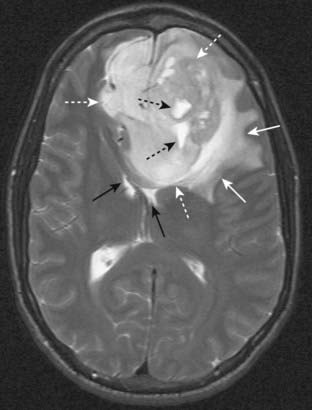

Figure 20-5 Metastatic melanoma.

Sagittal T1-weighted image of the brain demonstrates a bright mass (solid white arrow) in the frontal lobe representing metastatic melanoma. Notice that both the yellow bone marrow within the skull (solid black arrow) and the overlying subcutaneous fat (dotted white arrow) are bright. We can tell that this is a T1-weighted image because the CSF in the lateral ventricles is dark (open white arrow).

Figure 20-6 Glioblastoma multiforme with surrounding edema.

Axial T2-weighted image demonstrates bright vasogenic type edema (solid white arrows) surrounding a large, lobulated frontal lobe mass (dotted white arrows) representing glioblastoma multiforme, an aggressive brain tumor. There are a few bright areas of cystic degeneration (dotted black arrows) within this mass. The frontal horns of the lateral ventricles are compressed (solid black arrows).